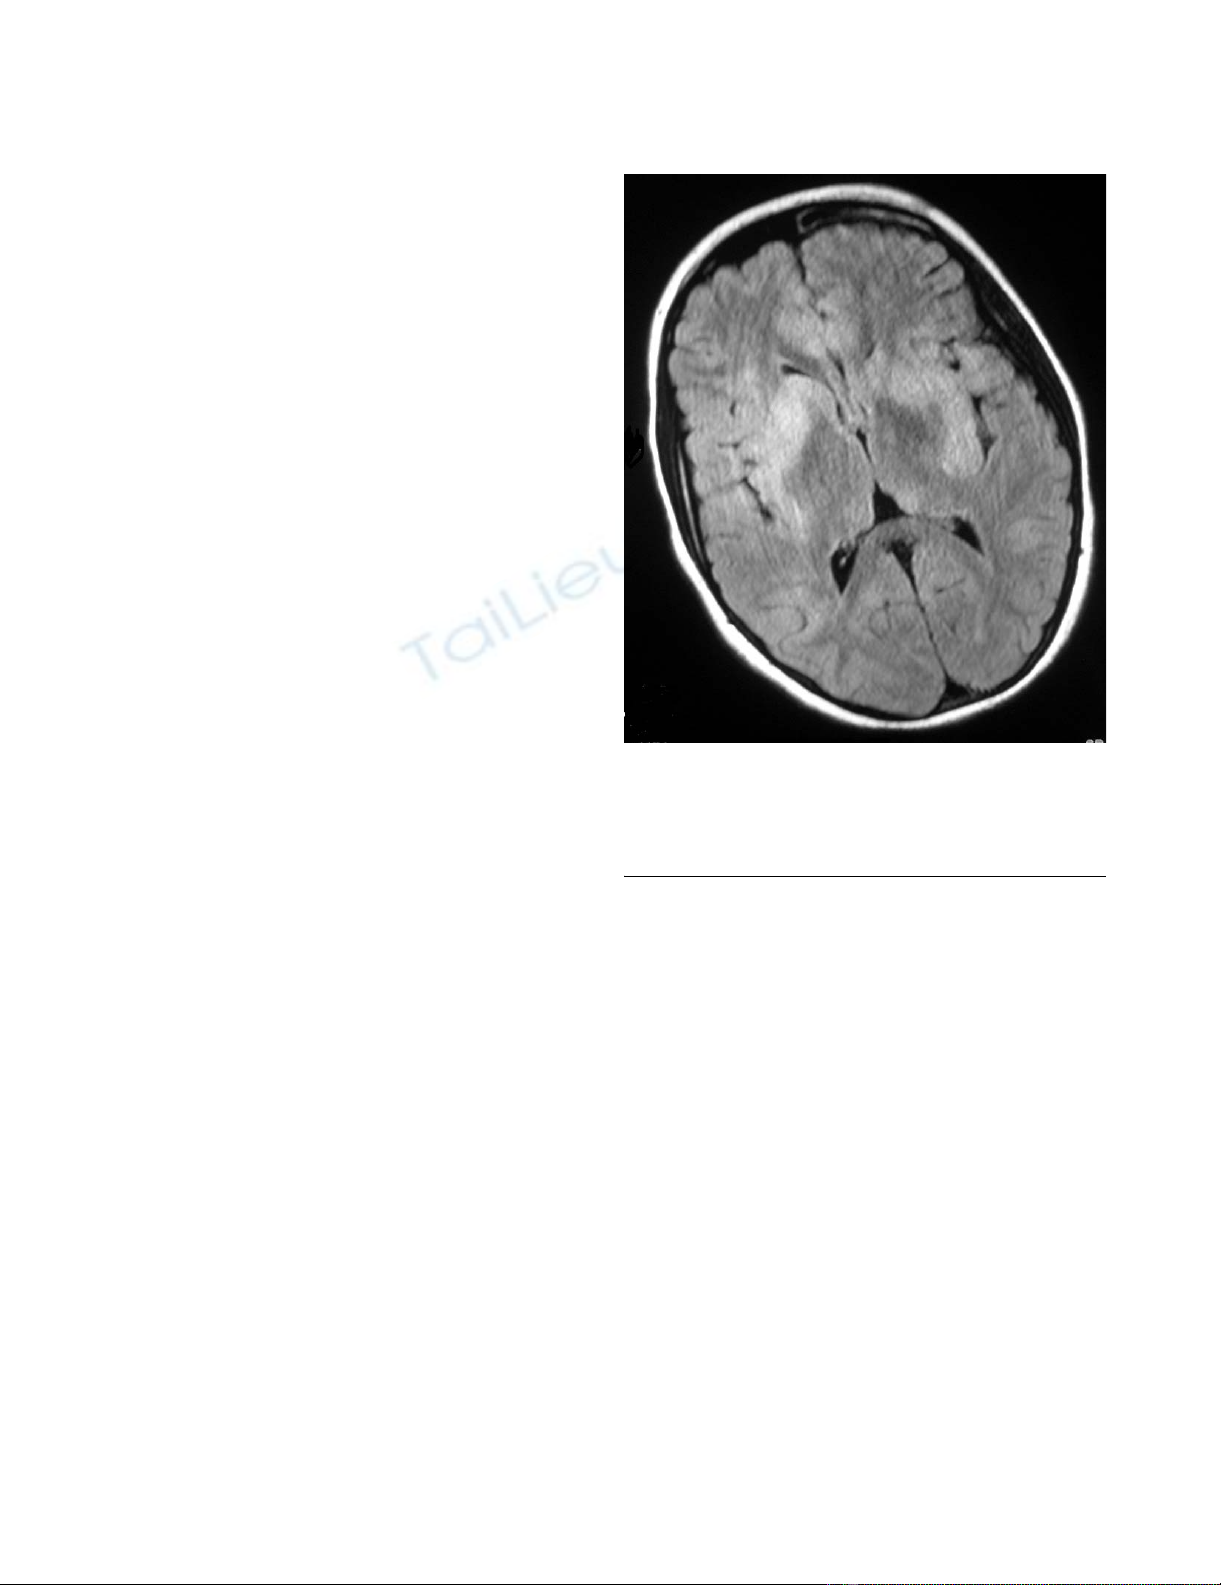

Axial FLAIR sequence magnetic resonance image of brain at admissionFigure 1

Axial FLAIR sequence magnetic resonance image of

brain at admission. There are hyperintense multifocal

lesions in the deep grey nuclei, subcortical white matter and

cortex.

Initial MR imaging showed diffuse involvement of the

CNS (Figures 1 and 2). The spinal cord was diffusely swol-

len showing central cord T2 hyperintensity from C1 to the

conus. There were multifocal grey and white matter

lesions in the cerebral cortex, subcortical areas and cere-

bellum which showed diffuse gadolinium enhancement.

The appearances were consistent with an infective or

inflammatory encephalomyelitis, but the girl's remote

history and presentation raised the concern of a recurrent

CNS relapse of ALL.